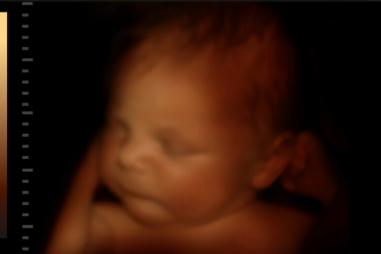

Unborn-baby-late-term-e1713177014919-810x500.jpeg

Kultúra života

Skupina za život spúšťa kampaň na spievanie vianočných kolied pred interrupčnými továrňami

22.12.2024 USA

Skupina na ochranu života organizuje kampaň, v rámci ktorej sa budú pri príležitosti osláv Narodenia Pána spievať vianočné koledy pred potratovými klinikami.   V decembri tohto roku vyzvala…